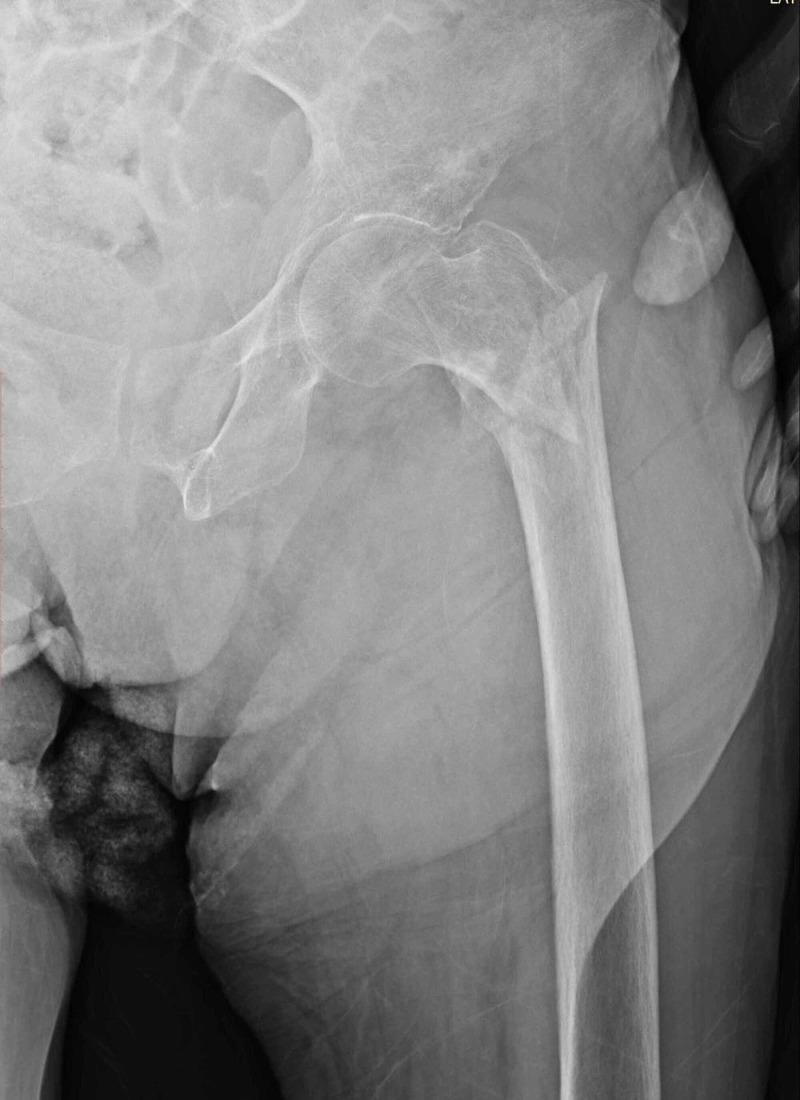

Comparison of Cementless Calcar-Replacement Hemiarthroplasty With Proximal Femoral Nail for the Treatment of Unstable Intertrochanteric Fractures at Older Age Group.

The aim of this study was to compare the outcomes of unstable intertrochanteric femur fractures treated with cementless calcar-replacement bipolar hemiarthroplasty (CRH) and proximal femoral nail (PFN) in elderly patients.

All consecutive unstable intertrochanteric fractures treated with cementless CRH or PFN at our institution between January 2015 and January 2019 were reviewed retrospectively. The primary outcome measures were postoperative complications, reoperation rate, and hip function. The secondary outcome measures were intraoperative blood loss, transfusion rate, surgical time, hospital stay, and two- year mortality.

Ninety-four patients in the hemiarthroplasty group and 77 patients in the PFN group were included for analysis. There were no significant differences between the two groups regarding the complications, ASA score, and reoperation rate. Significant differences were found between hemiarthroplasty and PFN group in comparison of the average length of hospital stay (P < 0.05), time from hospitalization to operation (P < 0.05), intraoperative blood loss (P < 0.001), transfusion rate (P < 0.001), operation time (P < 0.001), Harris Hip Score (HHS; P < 0.001), and two-year mortality (P < 0.05).

Both hemiarthroplasty and PFN produce satisfactory results in surgically treated unstable intertrochanteric femur fractures in the elderly. Both groups are associated with their own complications, but in the PFN group, better functional results, less surgery-related trauma, and lower mortality rates are the main advantages.